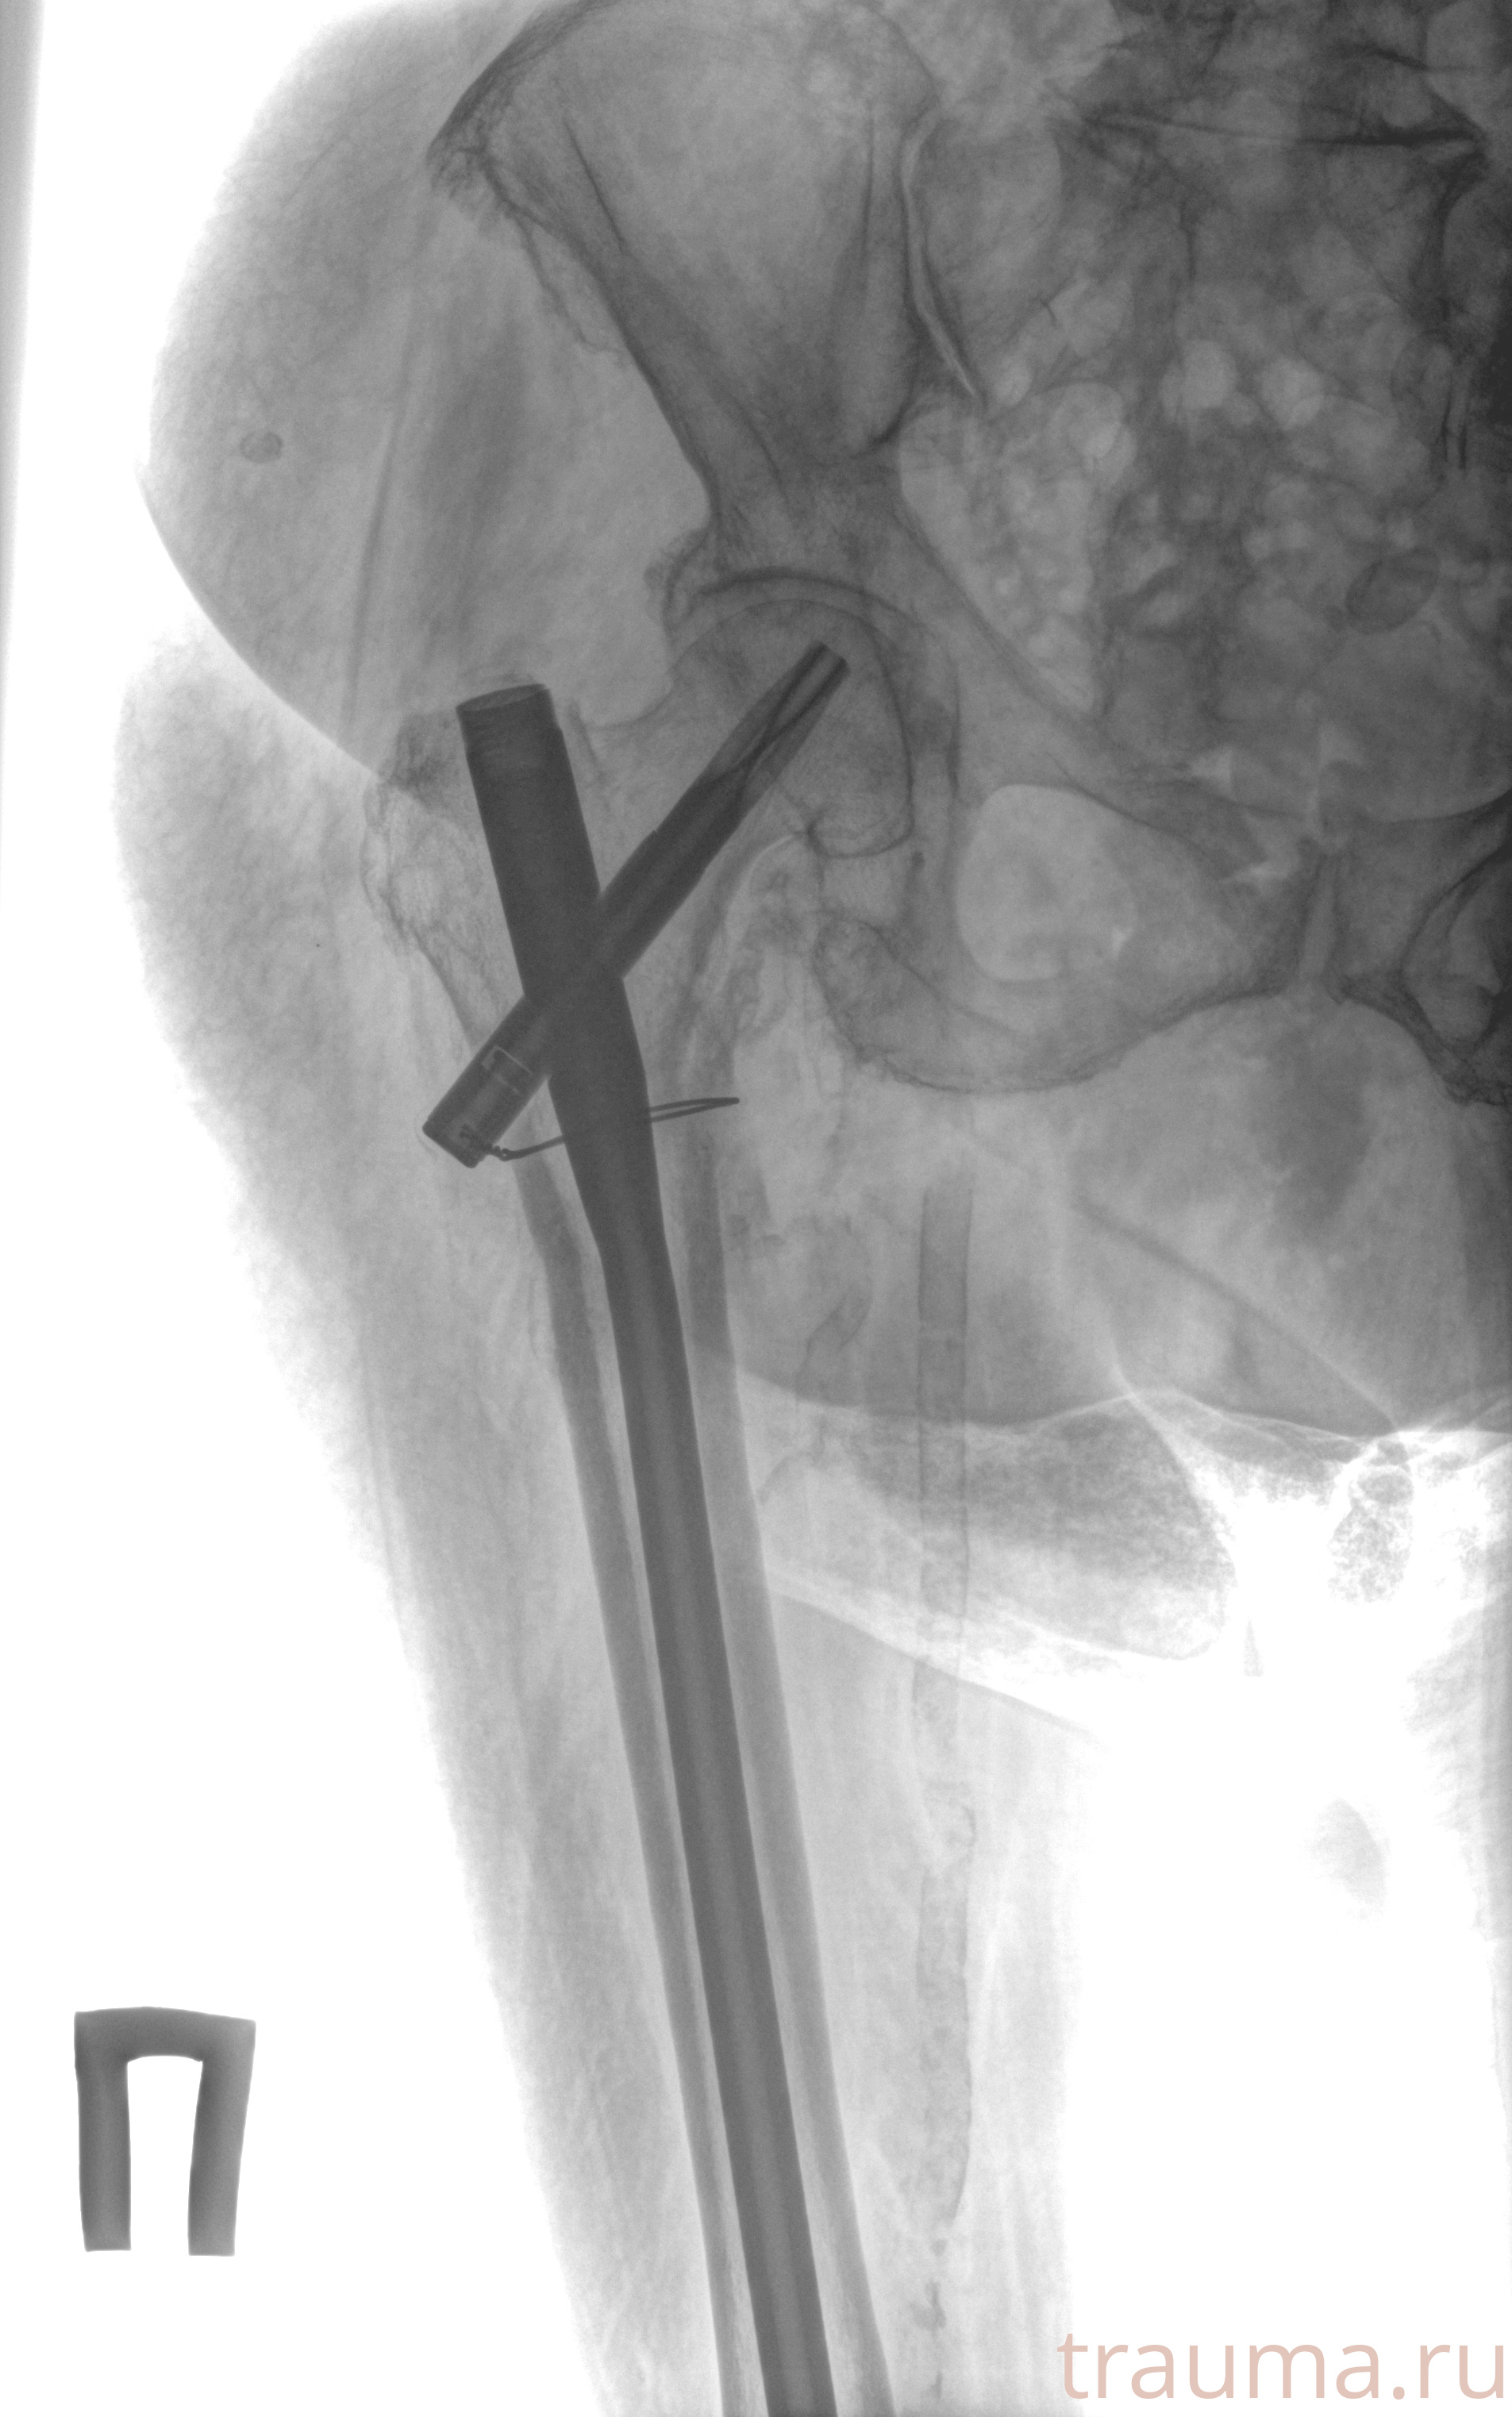

Рентгенограммы